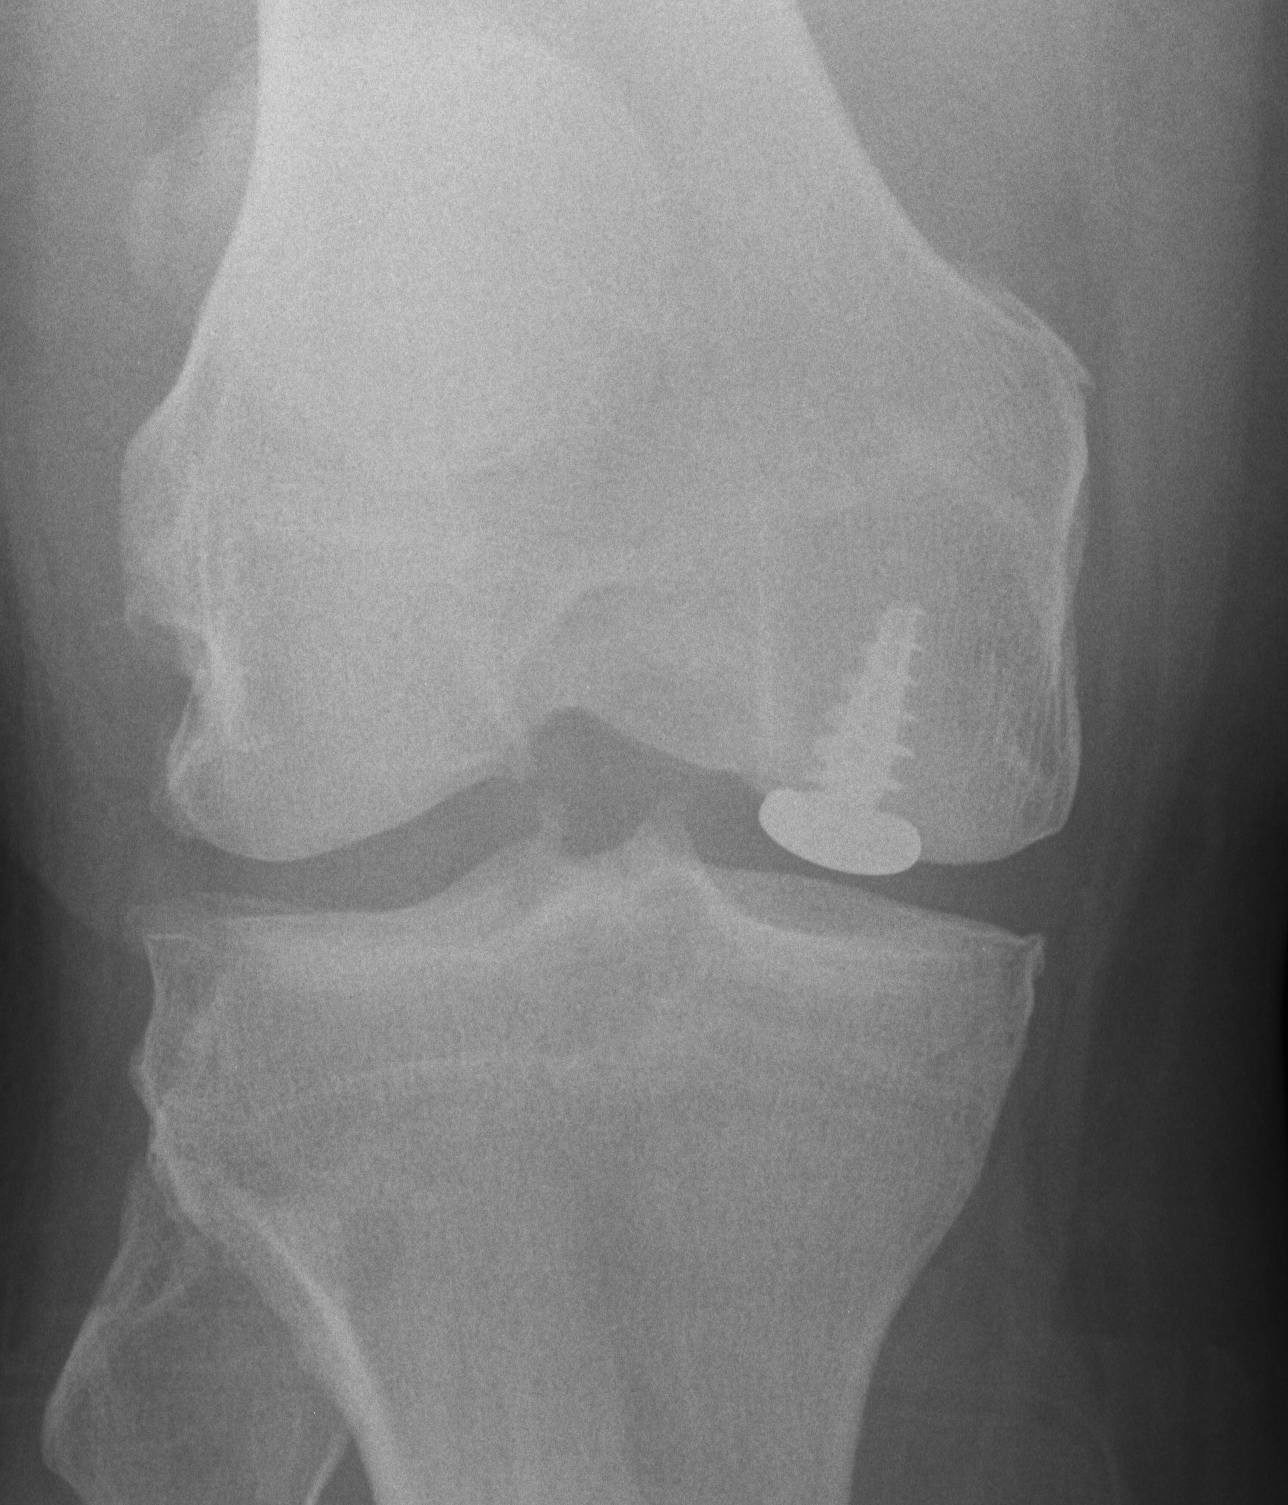

Osteochondral allograft

Principle

Indication

- very large, non contained defects

- previous failed cartilage procedures

Advantage

- restore anatomic contour

- nil donor site morbidity

- viable chondrocytes on fresh allograft < 30 days

Pre and post OCA with HTO

Use CT to get appropriate size graft

Match curvature of radius of donor site

Press fit